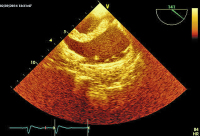

Apikaler Vierkammerblick

Abbildung 2: Apikaler Vierkammerblick: Lange echoreiche, anscheinlich am Vorhofseptum fixierte Masse prolabiert in die rechte und (weniger sichtbar) in die linke Kammer.